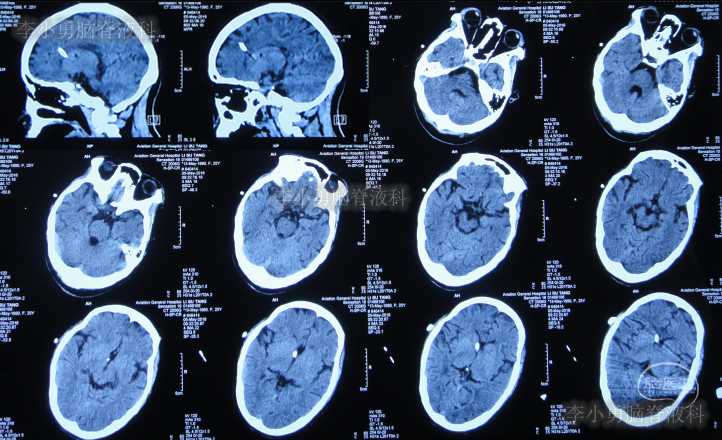

图-1:2016年3月18日头颅CT

第三家医院第2次建议回家观察1周后即2016年4月3日,症状仍未缓解反而越来越重,于是,就诊于第四家位于上海市徐汇区的某三甲医院,查头颅CT后(图-2)“认为无明显异常”,怀疑癫痫。

图-2:2016年4月3日头颅CT

家属为进一步明确病因即2016年4月4日,第2次就诊并住入第二家的上海市静安区的某三甲医院,复查头颅影像后(图-3、图-4),给予按癫痫进行治疗。

图-3:2016年4月4日头颅CT

图-4:2016年4月4日头颅影像